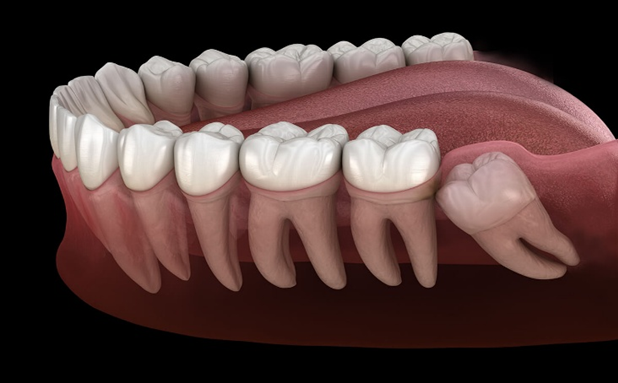

Wisdom teeth removal is a surgical dental procedure in which one or more wisdom teeth are extracted. These teeth may be impacted (trapped under the gums or bone), partially erupted, or misaligned. Removing problematic wisdom teeth helps maintain oral health and prevents future dental complications.

Removal of Multiple Wisdom Teeth

In cases where two, three, or all four wisdom teeth are problematic, multiple extractions may be recommended in a single visit. This approach reduces overall recovery time and future dental issues.